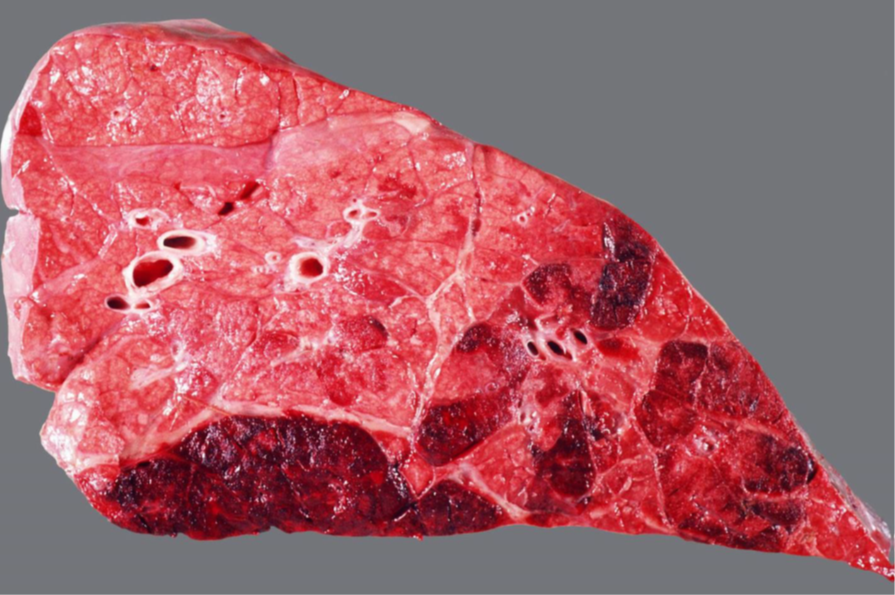

Rind, Lunge: hochgradige, akute bis subakute, multifokale, fibrinöse Pleuropneumonie

Beschreibung:

- Inset: kranioventral finden sich Parenchymund Pleuraveränderungen

- multifokale, gelblichrötliche Matten auf der Pleura (= Fibrin)

- Schnittfläche des Parenchyms: Läppchenbezogene Muster mit bunter Marmorierung

- die betroffenen Läppchen sind verfestigt

- einige Läppchen wirken trocken, andere Läppchen geben auf Druck dunkelrot- gräuliche Flüssigkeit frei

- Interstitien teilw. verbreitert und sulzig

Links (nur eine Hälfte) = A

Rechts (beide Hälften) = B

Schwein, Lunge: hochgradige, akute bis subakute, multifokale, fibrinöse Pleuropneumonie

- zufällige Verteilung der der Parenchym- und Pleuraveränderungen:

- in Spitzen- und Hauptlappen finden sich multiple landkartenähnliche Herde von roter bis dunkelroter Farbe und verfestigter Konsistenz

- multifokale, gelblichgraue Beläge auf der Pleura (= Fibrin), welche überwiegend mit den Herden des Parenchyms assoziiert sind

- Interstitien teilweise verbreitert

Ätiologie

- meistens, jedoch nicht ausschließlich, bakterielle Sekundär-Erreger nach primärer Virusinfektion

Erreger-Spektrum:

- vor allem gramnegative Bakterien (HAP-Gruppe), die Erreger besitzen Endotoxin (Lipopolysaccharid) und

bilden außerdem vielfach hochpotente Exotoxine (z.B. Apx-Toxine von Actinobacillus pleuropneumoniae)

H aemophilus (Glässerella) sp.

A ctinobacillus sp. (A. pleuropneumoniae = primäre Infektion beim Sw., außerdem A. suis und A. equuli)

P asteurella sp. (Mannheimia haemolytica (Rd.), P. multocida)

- außerdem aus der Familie der Pasteurellaceae: Histophilus somni (Rd.) und Bibersteinia trehalosi (Wdk.)

- Mycoplasmen (M. mycoides subsp. mycoides Small Colony Type, der Erreger der (anzeigepflichtigen!)

Lungenseuche des Rindes) und Mycoplasma bovis

- Pilze (Schimmelpilze)

Hintergrundwissen/ Infektionsweg/ Pathogenese

- die fibrinöse Pneumonie ist eine Form der Bronchopneumonie:

- aerogene Infektion > Bronchiolitis > peribronchioläre und endobronchioläre Fortleitung:

a) peribronchiolär > entlang der interstitiellen Lymphgefäße > Thrombose der Lymphgefäße > kein

Lymphabfluß (Gewebe ertrinkt und „stirbt“ im Ödem) > auf diesem Weg wird auch die Pleura erreicht

(Pleuropneumonie)

b) endobronchiolär > Alveolen füllen sich mit Entzündungsprodukten und Zellen an (Ödem, Fibrin, PMN,

Mø)

- makroskopisch typisch ist die kranioventrale Konsolidierung des Parenchyms; eine Ausnahme stellt die porzine

Pleuropneumonie* (APP) dar, weil die kaudalen Lungenlappen oft am stärksten betroffen sind

* meistens geht die fibrinöse Pneumonie mit einer fibrinösen Pleuritis einher > fibrinöse Pleuropneumonie

- neben der fibrinösen Komponente können auch Hämorrhagien und Nekrose (Sw: helle, landkartenähnliche und

trockene Herde in der gesamten Lunge) vorkommen

- die typische bunte Marmorierung des Parenchyms des Rindes entspricht dem klassischen (protrahierten) Ablauf in

vier Stadien:

1) Anschoppung

2) rote Hepatisation (leberähnlich, hepar = Leber)

3) graue Hepatisation

4) Organisation (Karnifikation)

- Komplikationen der fibrinösen (Pleuro-)Pneumonie: Sequester (v.a. Mykoplasmeninfektionen), Pleuraadhäsionen,

Abszesse bzw. Pleuraempyeme